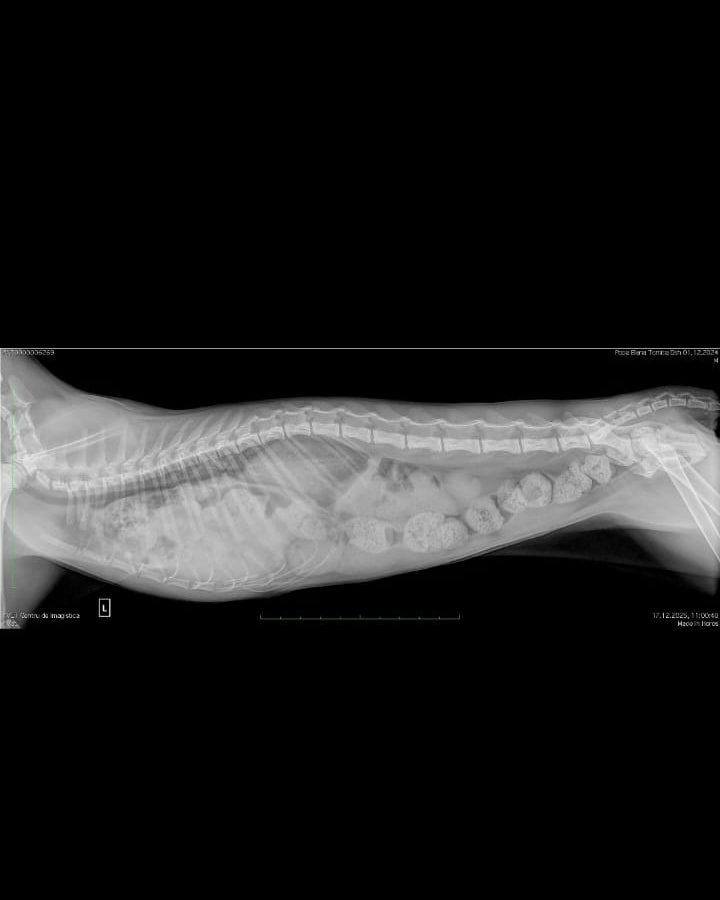

Așa cum se poate vedea pe radiografii, pisoiul are o hernie diafragmatică, organele sunt amestecate în cavitățile abdominală și toracică. Fără operație va muri.

Este plin de materii fecale. Va intra de urgență în operație la Radius Vet.